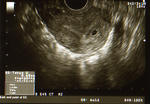

上の写真は今日の検査結果です。

右のほうにある小さな黒い丸がうちの子。

とにかく、正常妊娠でした。

体長はわずか0.65cm、妊娠約4週目で、心臓はまだできていません。

あと2週間くらいで心臓が動き始めて、それでようやく妊娠といえるのだそうです。